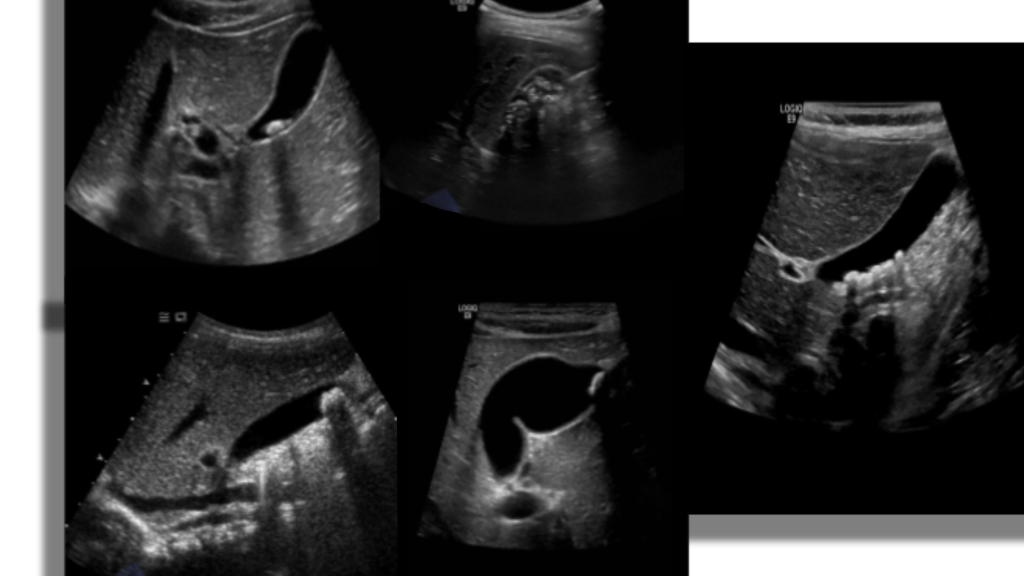

The gallbladder is an oblong pear shaped structure located on the underside of the liver. It is located at the level of the middle hepatic vein aka Cantlie’s line between segments IV and V. The normal distended gallbladder is approximately 7-10 cm in length and 4 cm in diameter. The capacity is usually 50 ml(1.8 fl oz) of bile. The GB is divided into neck, body and fundus, sonographic appearance is anechoic with an echogenic wall.

Increased through transmission is seen posterior to the gallbladder. The GB can be folded on itself in the shape of an S or have folds, a pouch in the fundus (Phyrigian cap) a pouch in the neck (Hartman’s pouch) and mucosal projections in the cystic duct (spiral valves of Heister).

Scanning the GB should include RUQ images of the Liver, biliary tree and gallbladder in sagittal and transverse planes.

Sonographically you’re going to see echogenic mobile structures in the GB which can be solitary or numerous and vary in size from small to large. Stones will have posterior acoustic shadowing. The gallbladder can be completely filled with stones obscuring the lumen leading to the wall echo shadow WES sign.

Mobility of the stone can be observed by scanning the patients in left lateral decubitus as well as supine. Scan the intra and extra hepatic biliary tree to look for dilatation, stones or both.